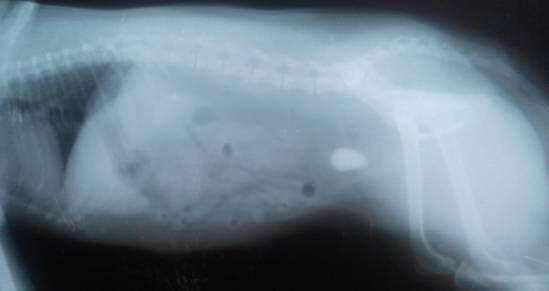

膀胱结石,也称泌尿系结石或尿石,是膀胱中矿物质和其他物质的异常积聚。犬尿含有许多通常保持溶解的物质。当尿液过浓时,这些溶解的物质会结晶。狗的常见尿晶有鸟粪石,草酸钙,尿酸盐,磷酸钙,硅酸盐和胱氨酸。随着时间的推移,晶体可以与细菌和其他物质结合形成膀胱结石。饮食,含水量,尿液pH值,膀胱感染,药物治疗,泌尿系结构和遗传学构造均可影响结石形成。膀胱结石很常见,特别是在年长的狗和公狗。当它们破坏膀胱内衬或堵塞通向外界的通道时,它们会造成问题,称为尿道。这导致尿液*退倒**,这是非常痛苦的,可能会导致膀胱破裂并可能致命。重要的是,作为狗的主人要认识到膀胱结石阻塞的迹象,这样就能尽快将他们的狗送到兽医那治疗。